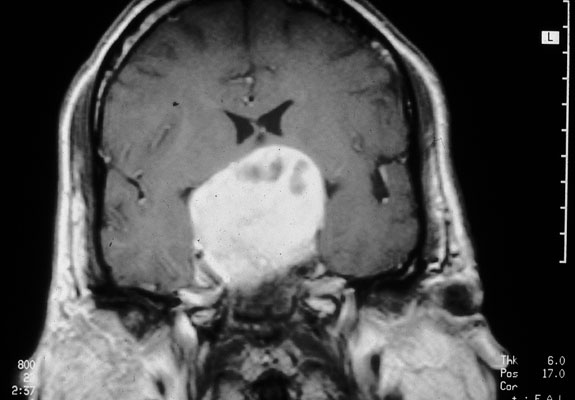

Macroadenoma of pituitary, MRI, frontal view

MRI scan of macroadenoma, frontal view.